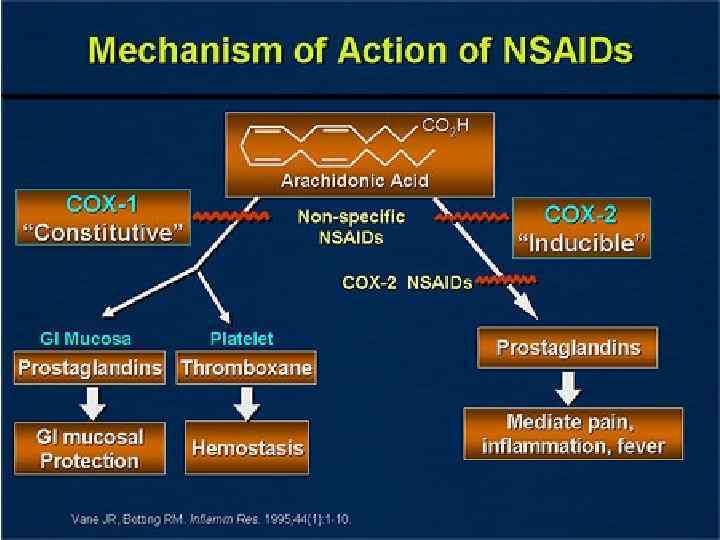

Anti-TNF & NSAIDS